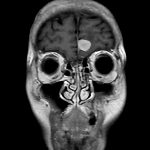

134

'19年10月

70代

左側頭葉膠芽腫

頭蓋内腫瘍摘出術

No.’19_35 手術前1

No.’19_35 手術前2